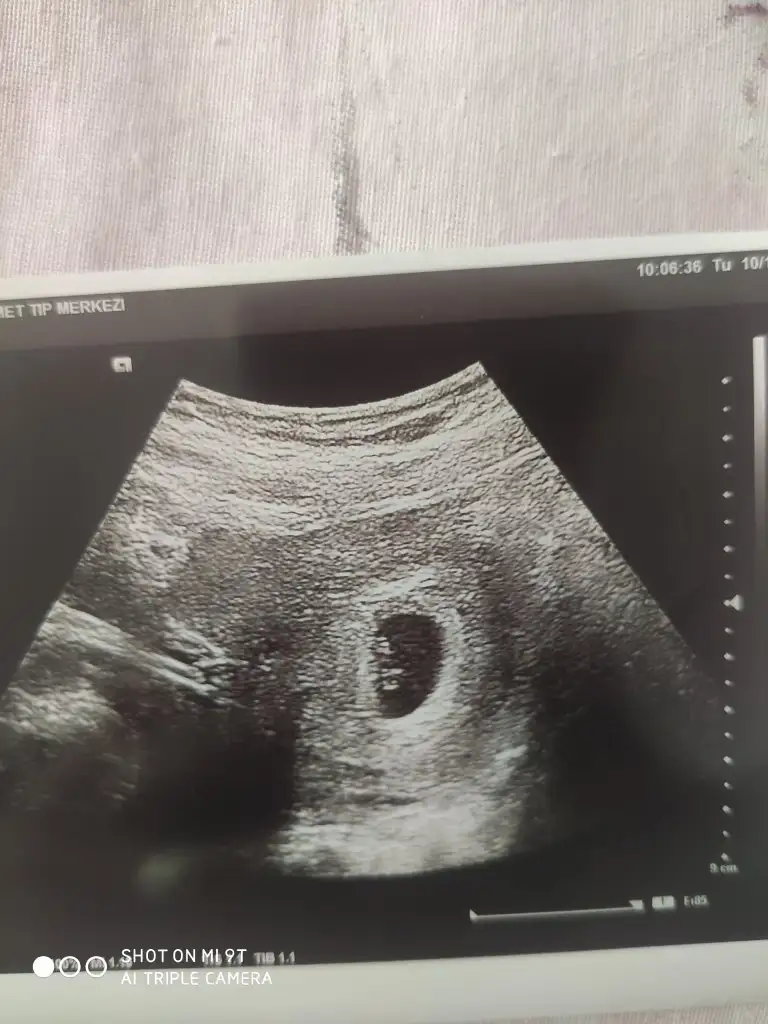

Başka USG paylaşın12 haftalık USG bu çok teşekkür ederim![]()

8 haftalık budaBaşka USG paylaşın![]()

Karından ise erkek vajinalsa kiz tabiki en iyi 11 12 13 haftalar8 haftalık buda

Karından bakıldı sonucu alınca yazarım size çok teşekkür ederimKarından ise erkek vajinalsa kiz tabiki en iyi 11 12 13 haftalar